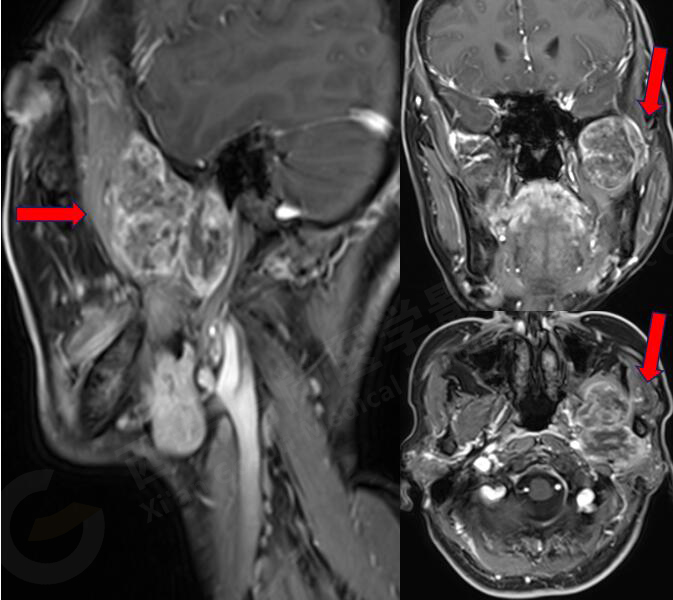

女,58歲,左側(cè)咀嚼肌間隙腫塊,鄰近翼板外側(cè)骨質(zhì)破壞;左側(cè)下頜升支內(nèi)側(cè)占位,皮質(zhì)旁骨軟骨來源。

MR圖像

MR診斷

左側(cè)翼腭窩、顳下窩占位,左側(cè)腮腺受壓變形,頸內(nèi)動脈稍受壓,考慮軟骨組織來源、良性病變。

此腫瘤位于左側(cè)翼腭窩、顳下窩,各序列均呈低信號,與翼突內(nèi)外側(cè)板、下頜骨關(guān)系密切,鄰近下頜骨骨皮質(zhì)破壞,DWI像上呈較高信號,呈不均勻中度強化,因此考慮軟骨來源或肌纖維來源,良性可能性大。